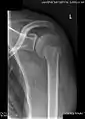

X-ray at left shows anterior dislocation in a young man after trying to get up from his bed. X-ray at right shows same shoulder after reduction and internal rotation, revealing both a bony Bankart lesion and a Hill-Sachs lesion.